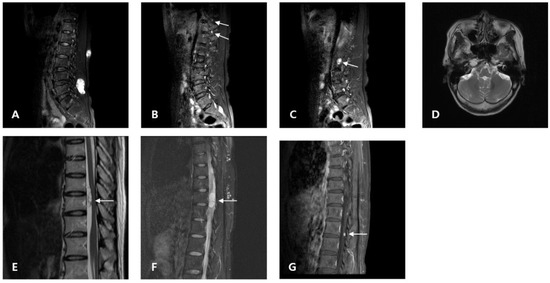

2. Case Presentation

2.1. Clinical Presentation (Proband)

2.2. Clinical Presentation (Daughter)